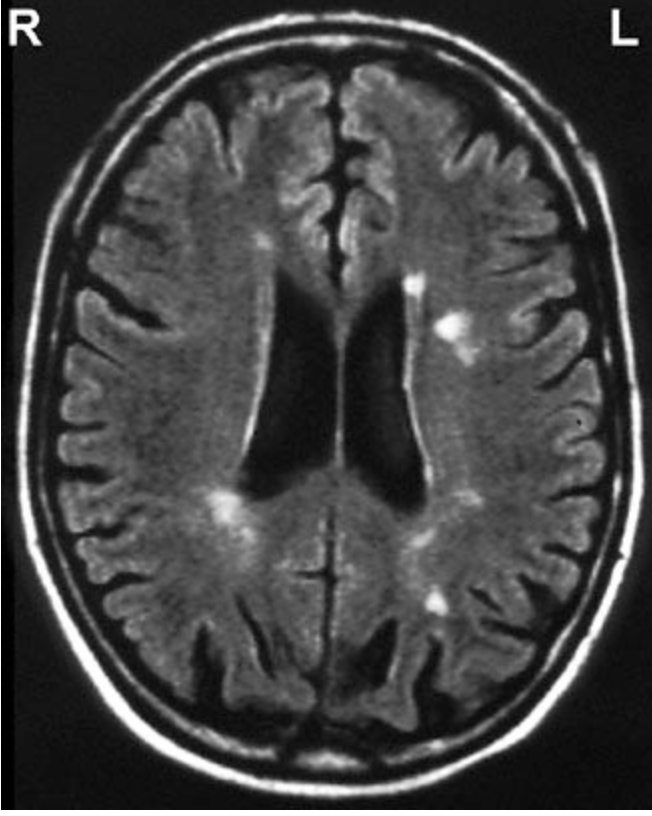

A 32-year-old woman comes to the physician because of weakness in her right leg that began 1 week ago and has resolved over the past 24 hours. She is currently asymptomatic. Two years ago, she had tingling in both hands and an “electric-like” sensation down her spine when she flexed her neck; her symptoms resolved after 3 weeks. Six months ago, she had visual loss in her right eye and pain with eye movement. Examination at that time showed a right central scotoma that resolved after 2 weeks. She has a history of mitral valve prolapse. She takes no medications. Her pulse is 64/min and regular, and blood pressure is 100/60 mm Hg. Cardiac examination shows a systolic click. Funduscopic examination shows mild pallor of the right optic disc; there is no afferent pupillary defect. Muscle strength is normal. Deep tendon reflexes are 2 in the upper extremities and 3 in the lower extremities. Babinski sign is present on the right. An MRI of the brain is shown. Which of the following is the most appropriate treatment for this patient?